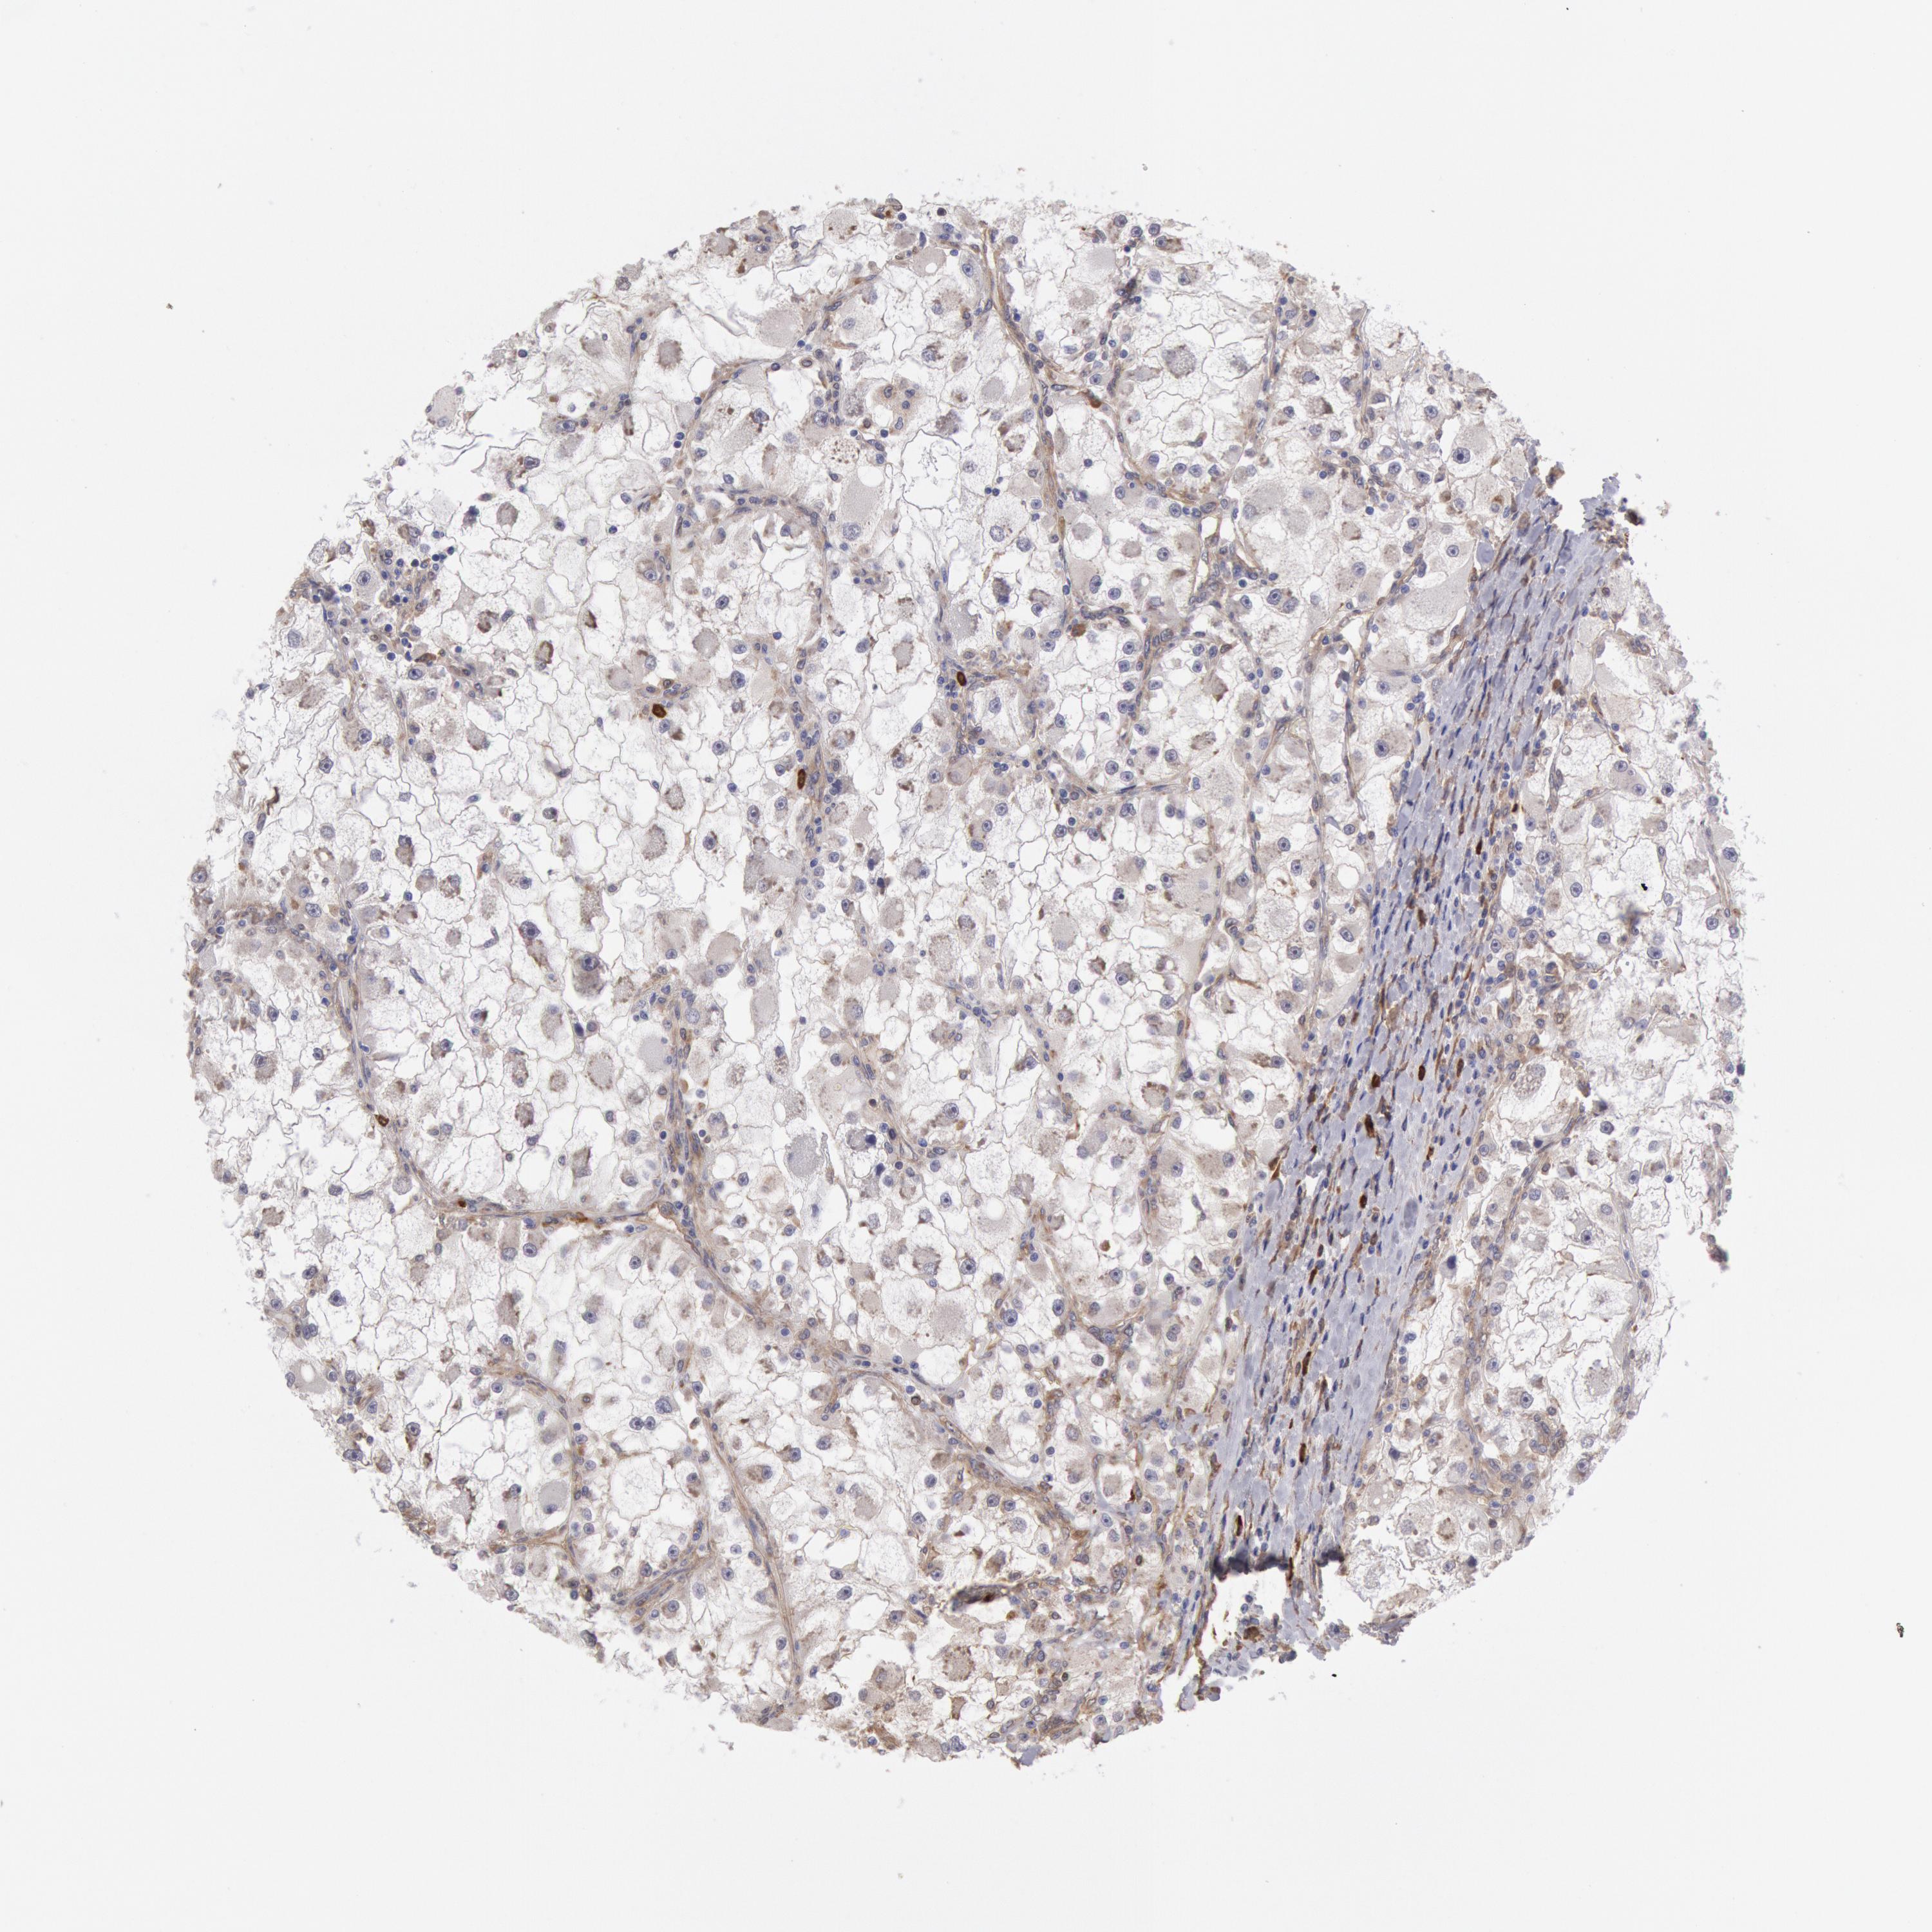

KIDNEY RENAL CLEAR CELL CARCINOMA (VALIDATION) - Interactive survival scatter ploti

The Survival Scatter plot shows the clinical status (i.e. dead or alive) for all individuals in the patient cohort, based on the same data that underlies the corresponding Kaplan-Meier plots. Patients that are alive at last time for follow-up are shown in blue and patients who have died during the study are shown in red.

The x-axis shows the expression levels (FPKM) of the investigated gene in the tumor tissue at the time of diagnosis. The y-axis shows the follow-up time after diagnosis (years). Both axes are complimented with kernel density curves demonstrating the data density over the axes. The top density plot shows the expression levels (FPKM) distribution among dead (red) and alive patients (blue). The right density plot shows the data density of the survived years of dead patients with high and low expression levels respectively, stratified using the cutoff indicated by the vertical dashed line through the Survival Scatter plot. This cutoff is automatically defined based on the FPKM cutoff that minimizes the p-score. The cutoff can be changed by dragging the vertical line or by entering a cutoff value in the square labeled "Current cut-off".

Under the Survival Scatter plot the p-score landscape (black curve; left axis) is shown together with dead median separation (red curve; right axis). Dead median separation is the difference in median mRNA expression between patients who have died with high and low expression, respectively. It is calculated as follows: median FPKM expression of dead patients with high expression - median FPKM expression of dead patients with low expression. This is intended to aid the user in visually exploring custom cutoffs and the associated p-scores and dead median separation.

Individual patient data is displayed and can be filtered by clicking on one or more of the category buttons on the top of the page. Categories describing expression level and patient information include: high, low, alive, dead, female, male and tumor stages. The scale of the x-axis can be toggled between linear and log-scale by clicking on the "x log" button. Mouse-over function shows TCGA ID, patient information and mRNA expression (FPKM) for each patient.

& Survival analysisi

Kaplan-Meier plots summarize results from analysis of correlation between mRNA expression level and patient survival. Patients were divided based on level of expression into one of the two groups "low" (under cut off) or "high" (over cut off). X-axis shows time for survival (years) and y-axis shows the probability of survival, where 1.0 corresponds to 100 percent.

CCDC50 is not prognostic in Kidney Renal Clear Cell Carcinoma (validation)

Best expression cut offi

Based on the FPKM value of each gene, patients were classified into two groups and association between prognosis (survival) and gene expression (FPKM) was examined. The best expression cut-off refers the FPKM value that yields maximal difference with regard to survival between the two groups at the lowest log-rank P-value. Best expression cut-off was selected based on survival analysis .

When clicking on this number, the vertical dashed line indicating cut-off, the interactive survival plot, and the Kaplan-Meier curve will be adjusted to show results based on the best expression cut-off.

: 72.82

TCGA RNA samplesi

RNA-seq data is reported as average FPKM (number Fragments Per Kilobase of exon per Million reads), generated by the The Cancer Genome Atlas (TCGA) .

Normal distribution across the dataset is visualized with box plots, shown as median and 25th and 75th percentiles. Points are displayed as outliers if they are above or below 1.5 times the interquartile range. FPKM values of the individual samples are presented next to the box plot.

Average pTPM 72.9

Number of samples 100